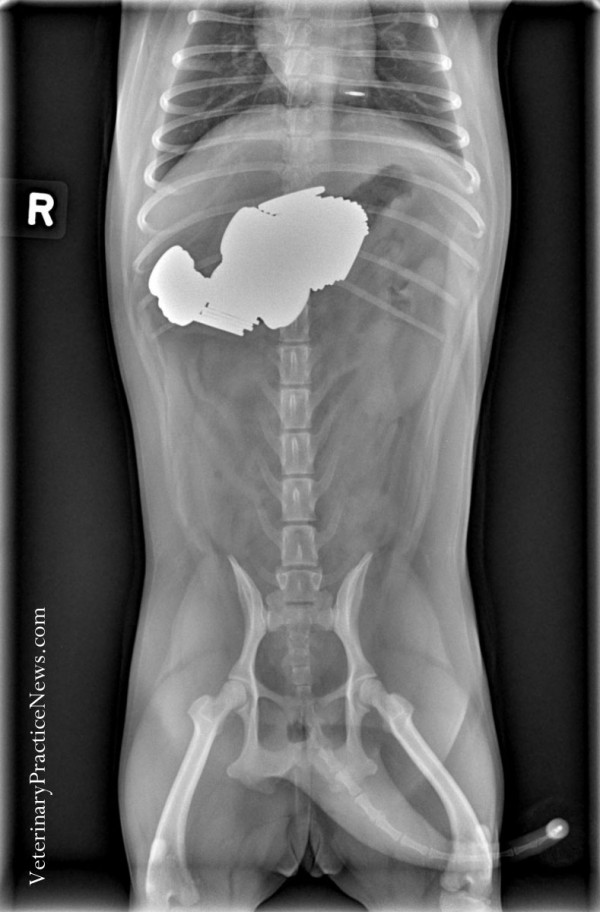

Собака съела 43 с половиной носка

В общей сложности эта собака съела монет на 1,29 долл из которых 104 пенни и 1 четвертак